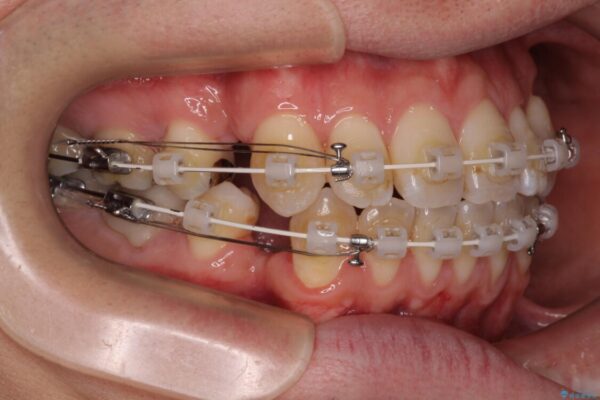

治療途中

• 口元の突出感を改善!目立ちにくいワイヤー矯正で自信を持てる自然な横顔に 治療途中画像

装置は、透明感のあるクリアブラケットとホワイトコーティングされたワイヤーを使用した、目立ちにくい審美装置を選択。

周囲に気づかれにくく、日常生活にも自然に溶け込みます。